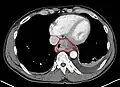

Additional testing is needed to assess how much the cancer has spread (see § Staging, below). Computed tomography (CT) of the chest, abdomen and pelvis can evaluate whether the cancer has spread to adjacent tissues or distant organs (especially liver and lymph nodes). The sensitivity of a CT scan is limited by its ability to detect masses (e.g. enlarged lymph nodes or involved organs) generally larger than 1 cm.[44][45] Positron emission tomography is also used to estimate the extent of the disease and is regarded as more precise than CT alone.[46] PET/MR as a novel modality has shown promising results in preoperative staging with fair feasibility and good correlation in comparison to PET/CT. It can enhance tissue differentiation with lowering the radiation dose to the patient.[47] Esophageal endoscopic ultrasound can provide staging information regarding the level of tumor invasion, and possible spread to regional lymph nodes.

Contrast CT scan showing an esophageal tumor (axial view)